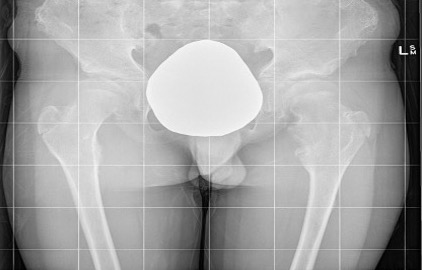

Hip

- coxa valga

- neck short & broad

Mult OC hipHip Osteochondroma

Hip HME

Issues

Coxa valga

Hip subluxation

Guided growth

Hung et al J Paediatr Orthop 2023

- 12 patients with HME and coxa valga / hip subluxation

- guided growth improved neck shaft angles and epiphyseal angles